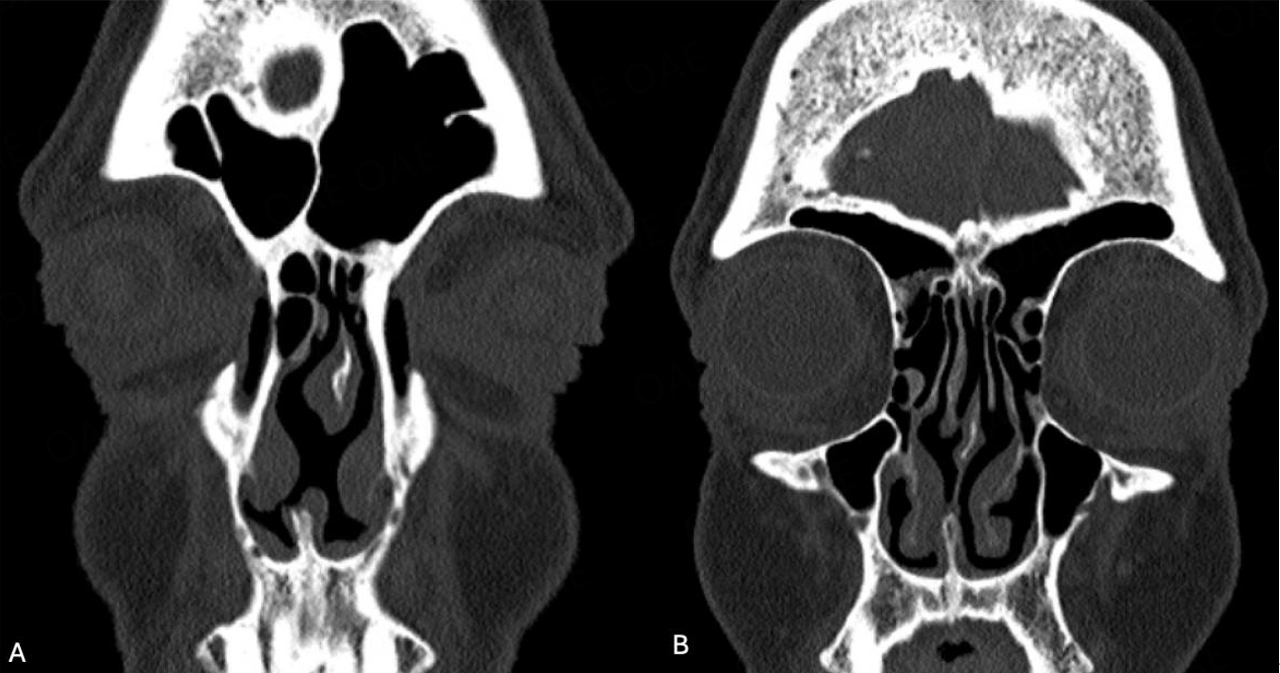

Despite substantial experience in closing perforations, attempted repair remains challenging when prior septal surgery has been performed regardless of the perforation size. Septal scarring due to one or more prior procedures can substantially impact the ability to develop surgical planes for intact mucosal elevation. The removal of bone and cartilage during septal surgery results in densely adherent and attenuated mucosa that can extend for a distance beyond the perforation margin. A slow and tedious dissection is common for perforations resulting from prior septal surgery. This condition is most problematic posteriorly, where a thin margin of fused mucosa can pose a substantial challenge to intact bilateral separation before reaching cartilage or bone located 1 cm or more posterior to the perforation mucosal margin [Figure 4]. Intact elevation of right and left mucosa is facilitated by the injection of saline or local anesthetic to widen the margin sharp separation with a #15 blade. The eight patients in this study for whom an interposition graft was not placed had prior septal surgery. Operative note review described the substantial difficulty in elevating mucosa intact in all patients, resulting in a tenuous single-layer repair that prevented the “interposing” of a tissue graft. The difference in perforation sizes for failed repairs between surgical and non-surgical etiologies noted in this study was significant. These clinical observations and measurement analysis findings support our impression that prior septal surgery increases the technical difficulty associated with flap closure procedures, irrespective of perforation size. The difference in failure rates between surgical and non-surgical (5.7% vs. 4.7%) etiologies found in this study was not significant and may, in part, reflect surgical experience.

Figure 4. Computed tomography (CT) scan coronal images of surgical etiology perforation 12 mm length by 9 mm height. (A) Image through perforation; (B) Image through thin posterior margin absent of cartilage; Patient opted for a customized septal button.